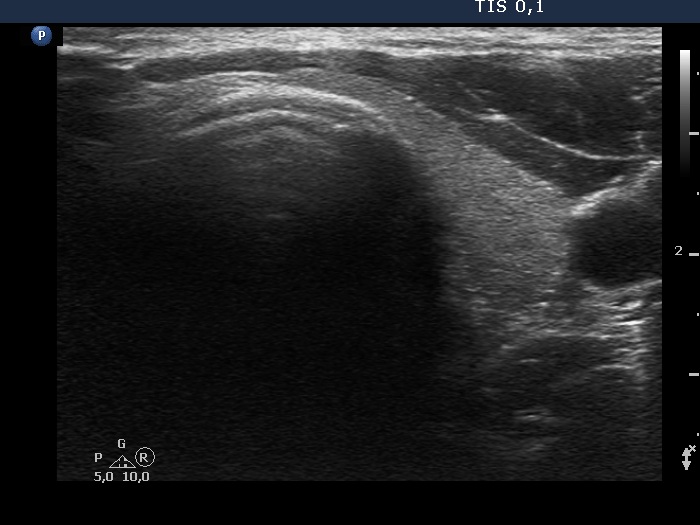

One year before the present examination (first row of images)

Ultrasonography. The thyroid was echonormal. A large nodule occupied almost the entire right lobe. This was an almost completely cyst with a tiny echonormal solid part at the ventral wall. The nodule had numerous large comet-tail artifacts and showed no vascularity. The dimensions of the nodule were 24x27x48 mm - 16.3 mL.

At the first examination, the nodule compressed the vessels running outside the nodule while on follow-up this compression was released, therefore the perinodular vascularity became visible.

The nonparallel orientation became parallel.